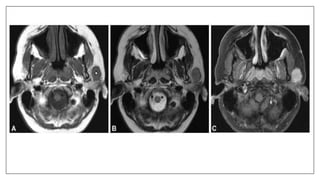

Metal artifacts: Braces

Braces may cause an artifact distant from the source. The axial proton density

and T2-weighted images exhibit horseshoe shaped artifacts. Note it is much

subtler on the T2 image.

Metal Artifact Causing Cone head Appearance

presence of a small metal clip on an elastic in the patients hair. Ferrous metal will cause a

magnetic field inhomogeneity which in turn causes a local signal void, often ringed by an

area of high signal intensity, as well as a distortion of the image. Once the metal was

removed the patients head returned to a more normal shape.

Patient Wearing Belt

The patient was wearing a metal-studded belt during this coronal T1-